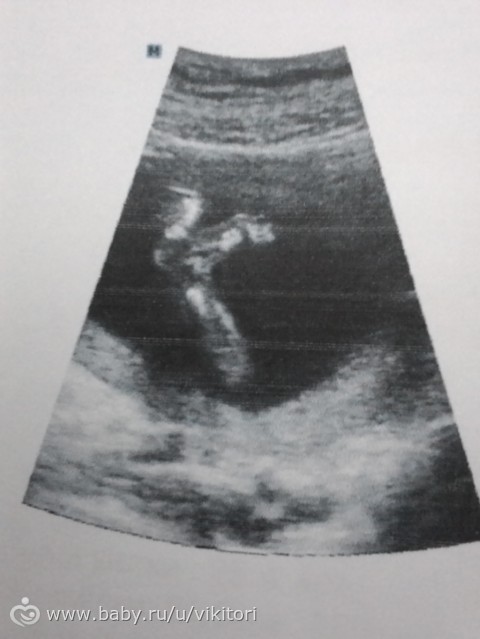

Наше УЗИ в 18 недель с фото))

Вчера ходили на УЗИ с любимым в 18 недель и 3 дня

Все у малыша хорошо, весит 230 грамм уже, очень активный, как юла врач сказала)

Плацента толщина в норме, степень зрелости 0, только вот плацента низко и тонус есть по передней стенке.

Ииии у нас точно доченька там растет))) Безумно рады с мужем, мечта сбылась наша))) А мамы наши так вообще рады, разрушила статистику у мужа в роду, а то у них одни пацаны рождались

Наша девочка не давала врачу сердечко её посмотреть никак, зато постоянно ноги раздвигала и попу показывала нам, мол смотрите я точно девочка, ноги длинные какие))

Сказали голова у доци будет кругленькая) Пальчики все на месте, органы без особенностей)

Вот только ЧСС 156 уд в мин, может быть и тахикардия, дальше посмотрим.

И вот наш профиль, смешнючая моя лапочка))